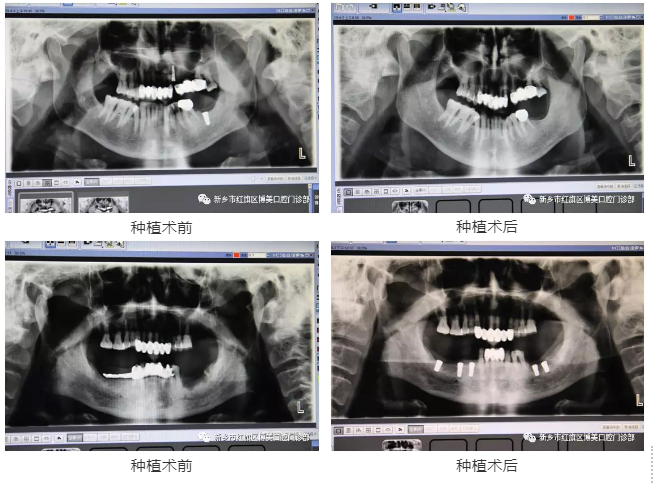

病例展示